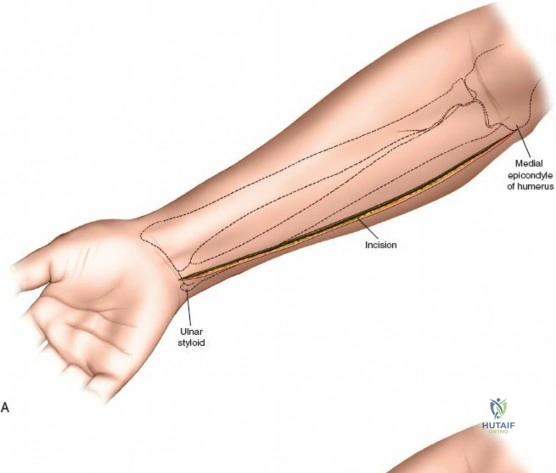

Incision: A curvilinear incision is made from the medial epicondyle, across the antecubital fossa, extending obliquely to the mid-volar aspect of the forearm, and then longitudinally down to the wrist crease, potentially extending into the palm to release the carpal tunnel. The incision should be generous, allowing for wide exposure.

- Key points: The proximal portion of the incision should curve gently to avoid crossing the elbow flexion crease at a right angle, which could lead to contracture. Distally, it should avoid cutting directly over the median nerve at the wrist.

This image shows the standard curvilinear incision for the volar approach, extending proximally from the medial epicondyle, gently crossing the antecubital fossa, and proceeding distally across the mid-forearm to the wrist.

- Key points: The proximal portion of the incision should curve gently to avoid crossing the elbow flexion crease at a right angle, which could lead to contracture. Distally, it should avoid cutting directly over the median nerve at the wrist.

Incision: A separate straight longitudinal incision is made over the dorsal aspect of the forearm, centered approximately between the ulna and radius, extending from just distal to the lateral epicondyle to the wrist.

This image shows the dorsal longitudinal incision, made directly over the extensor compartment, providing access for decompression. -